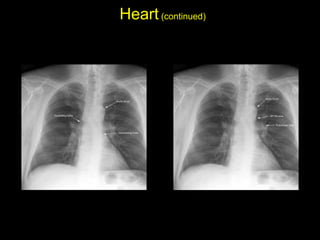

The document discusses the anatomy of the chest x-ray and CT scan by describing the lobes of the lungs and their locations. It also mentions the heart, mediastinum, hilum, and ribs. Several axial, coronal, and sagittal CT images are included with labels pointing out structures like the trachea, bronchi, lobes of the lungs, and fissures. In summary, the document provides an overview of lung and chest anatomy as seen on x-rays and CT scans through text descriptions and labeled medical images.